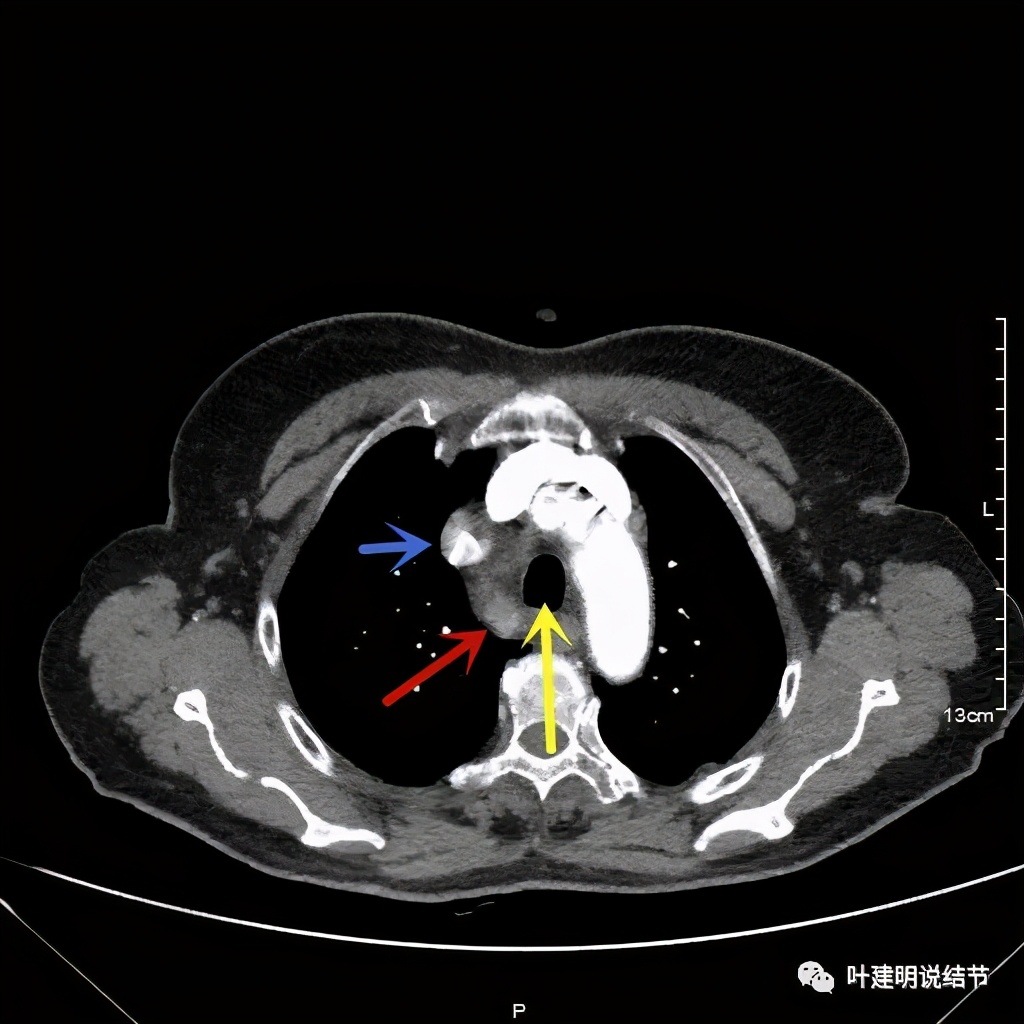

上图红色示肿瘤,黄色示气管,粉色示肿瘤与气管关系密切,桔色示左无名静脉,肿瘤密度不均

上图红色示肿瘤,黄色示气管,蓝色示上腔静脉